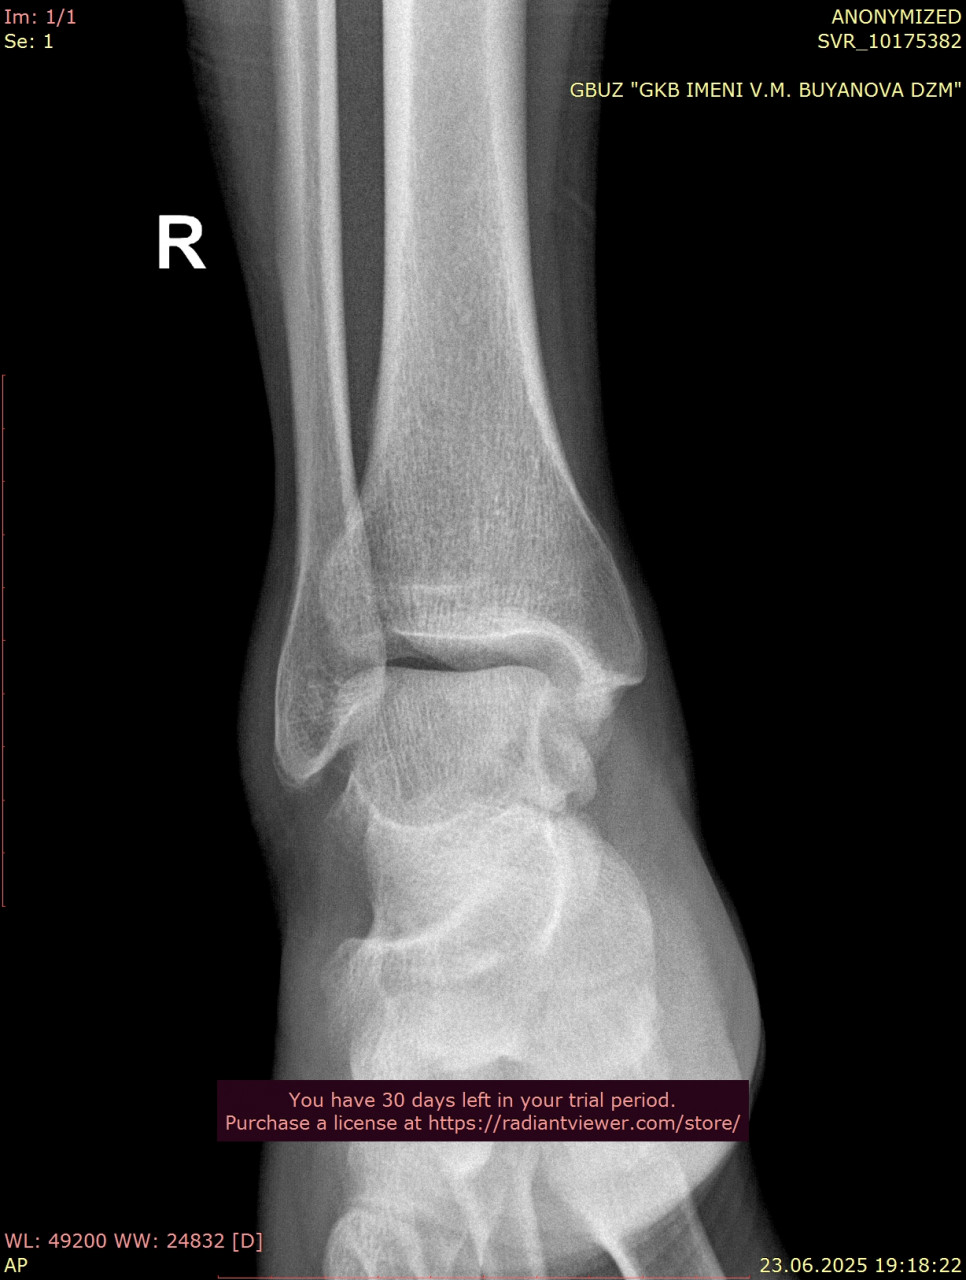

Посмотрите, пожалуйста, снимки стопы от 23.06.2025, когда был перелом, и спустя почти 11 недель от 04.09.2025. Как Вы считаете, переломы срослись нормально, или есть необходимость сделать еше один рентген в будущем? Можно ли переходить к обычному режиму нагрузок? У меня есть еще вторая проекция от 23.06.2025 и снимки голеностопного сустава, там тоже был перелом, но лимит сайта 3 файла. Остальные файлы могу прикрепить к Вашему ответу.

Посмотрите, пожалуйста, еще снимки голеностопного сустава от 23.06.2025, когда был перелом, и спустя почти 11 недель от 04.09.2025. Нормально ли сросся перелом, нужны ли еще снимки?